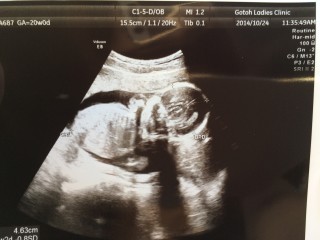

20週の健診でようやく性別が判明です。 303グラムの女の子。4人目で待望の女の子! エコー写真だけでパパはメロメロでした。

この日は、やっと待ちに待った性別が分かった日でした!待望の女の子でパパは既にエコー写真にさえ、メロメロ?毎晩名前を考える事が楽しくて仕方ありません。